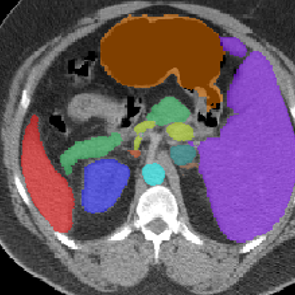

Visualization. We visualize 3D reconstruction results to check what HySparK learns in pre-training. As shown in Fig. 6, our method can almost reconstruct the different shapes of organs, bones, and other details from the very small portion of unmasked patches.

(a)

(b)

(c)

(d)

(e)

(f)